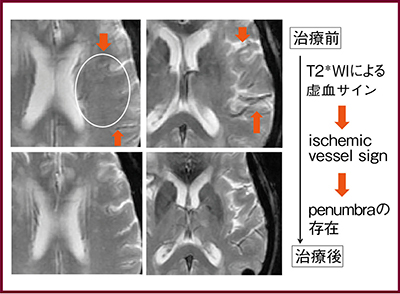

T2*強調画像では血栓部位の低信号(susceptibility vessel sign:図2a↓)が認められ塞栓の可能性が示唆されたが,ASLでは閉塞部位を示すvascular signの高信号(図2b↓)が認められた。また,虚血部位のT2*強調画像(図3)では虚血サイン(ischemic vessel sign)が認められ,ischemic penumbra(可逆的な前梗塞領域)の存在を示す所見である。

図3 治療前後のMR画像:T2*強調画像